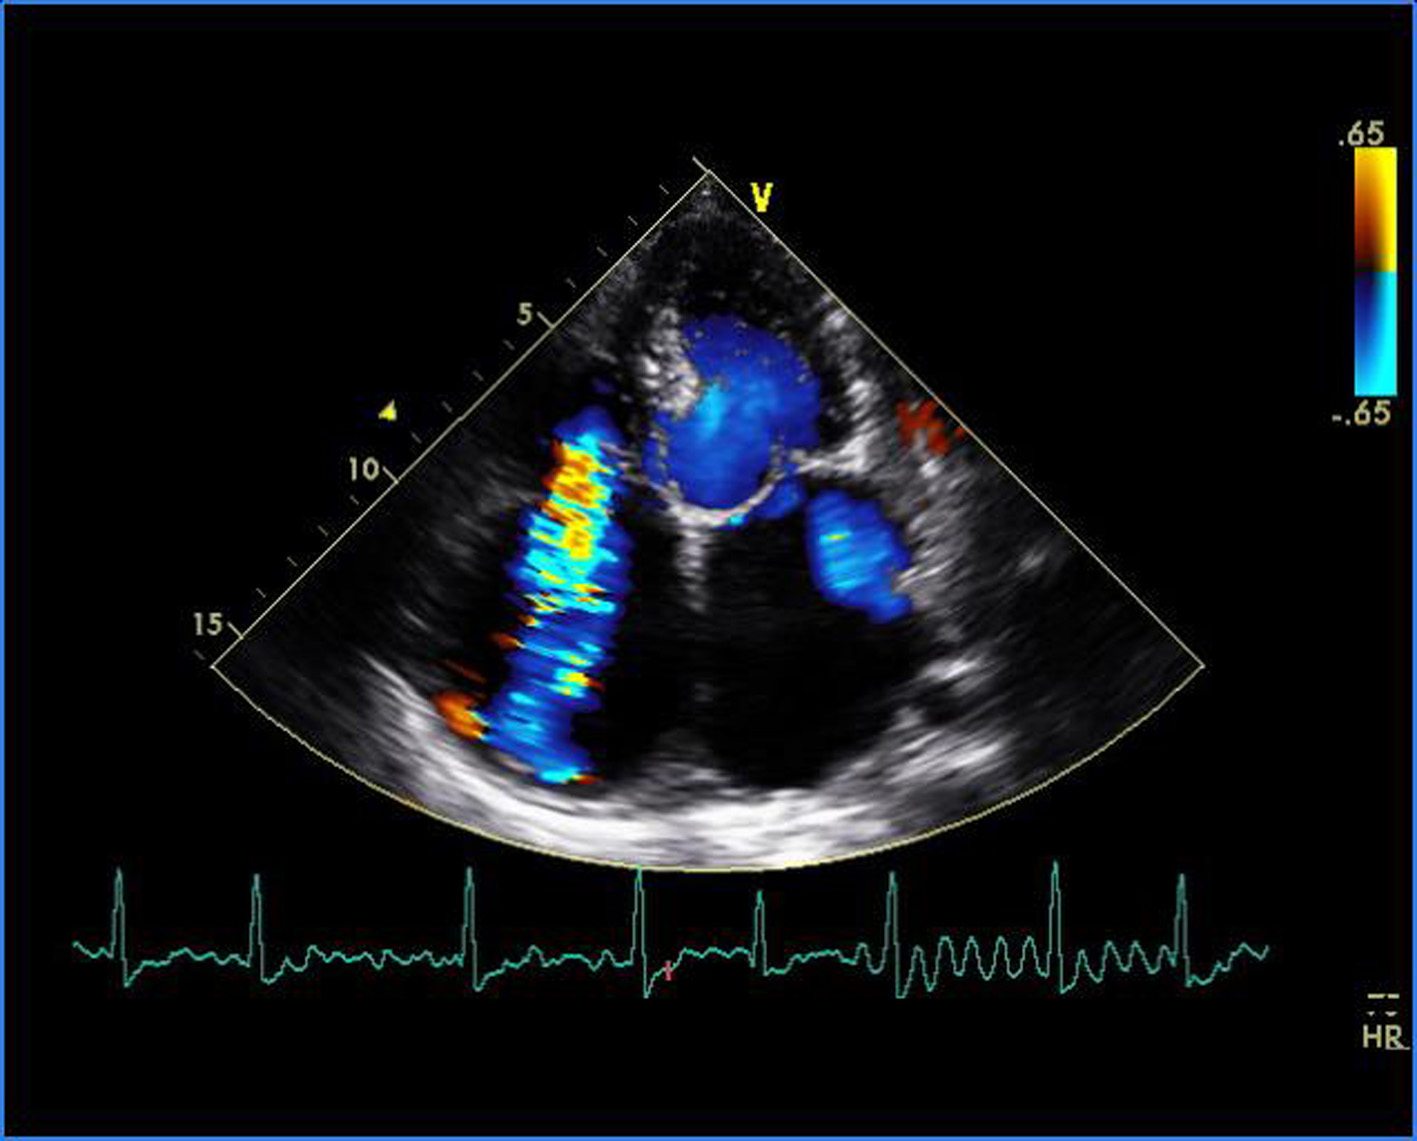

Figure 1. Transthoracic echocardiogram of apical four-chamber view showing thickened and doming mitral valve and tricuspid valve.

Malignant Rheumatic Heart Disease Presenting as Quadrivalvular Stenosis